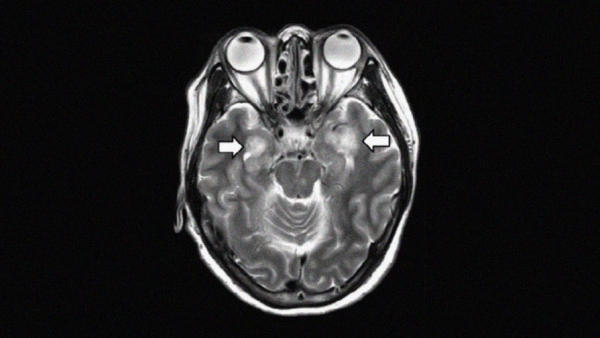

Radiological Society of North America